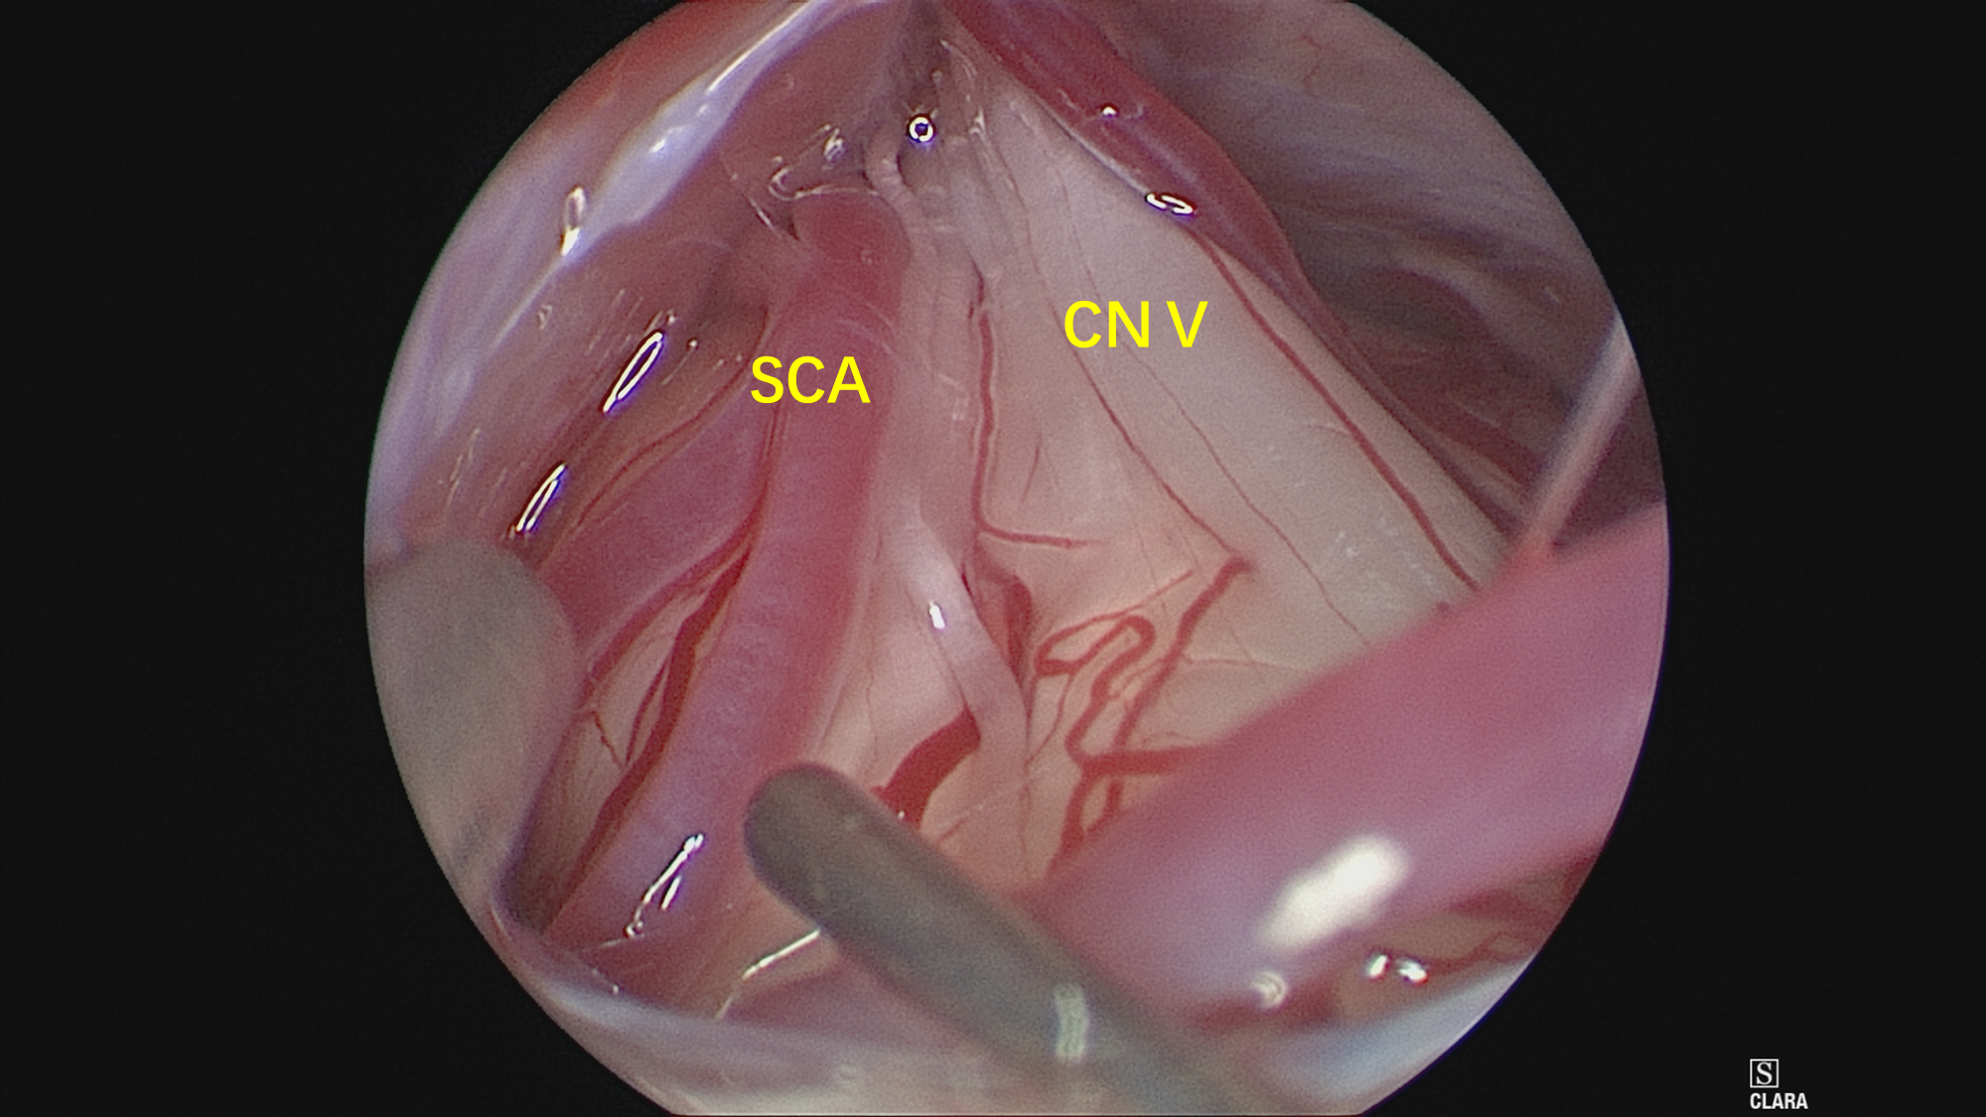

MRTA可见,小脑上动脉与右侧三叉神经关系密切,且与之紧贴,脑池空间(白色)狭小,三叉神经与岩骨距离近。

术中充分释放脑脊液,从面听神经与岩静脉之间的间隙观察三叉神经。

神经内镜抵近观察(岩静脉的阻挡迎刃而解,内镜的优势体现),岩骨、SCA与三叉神经紧贴,减压空间较小。

在不损伤岩静脉的前提下,将责任血管尽可能向小脑与天幕之间移位,使减压尽可能充分。